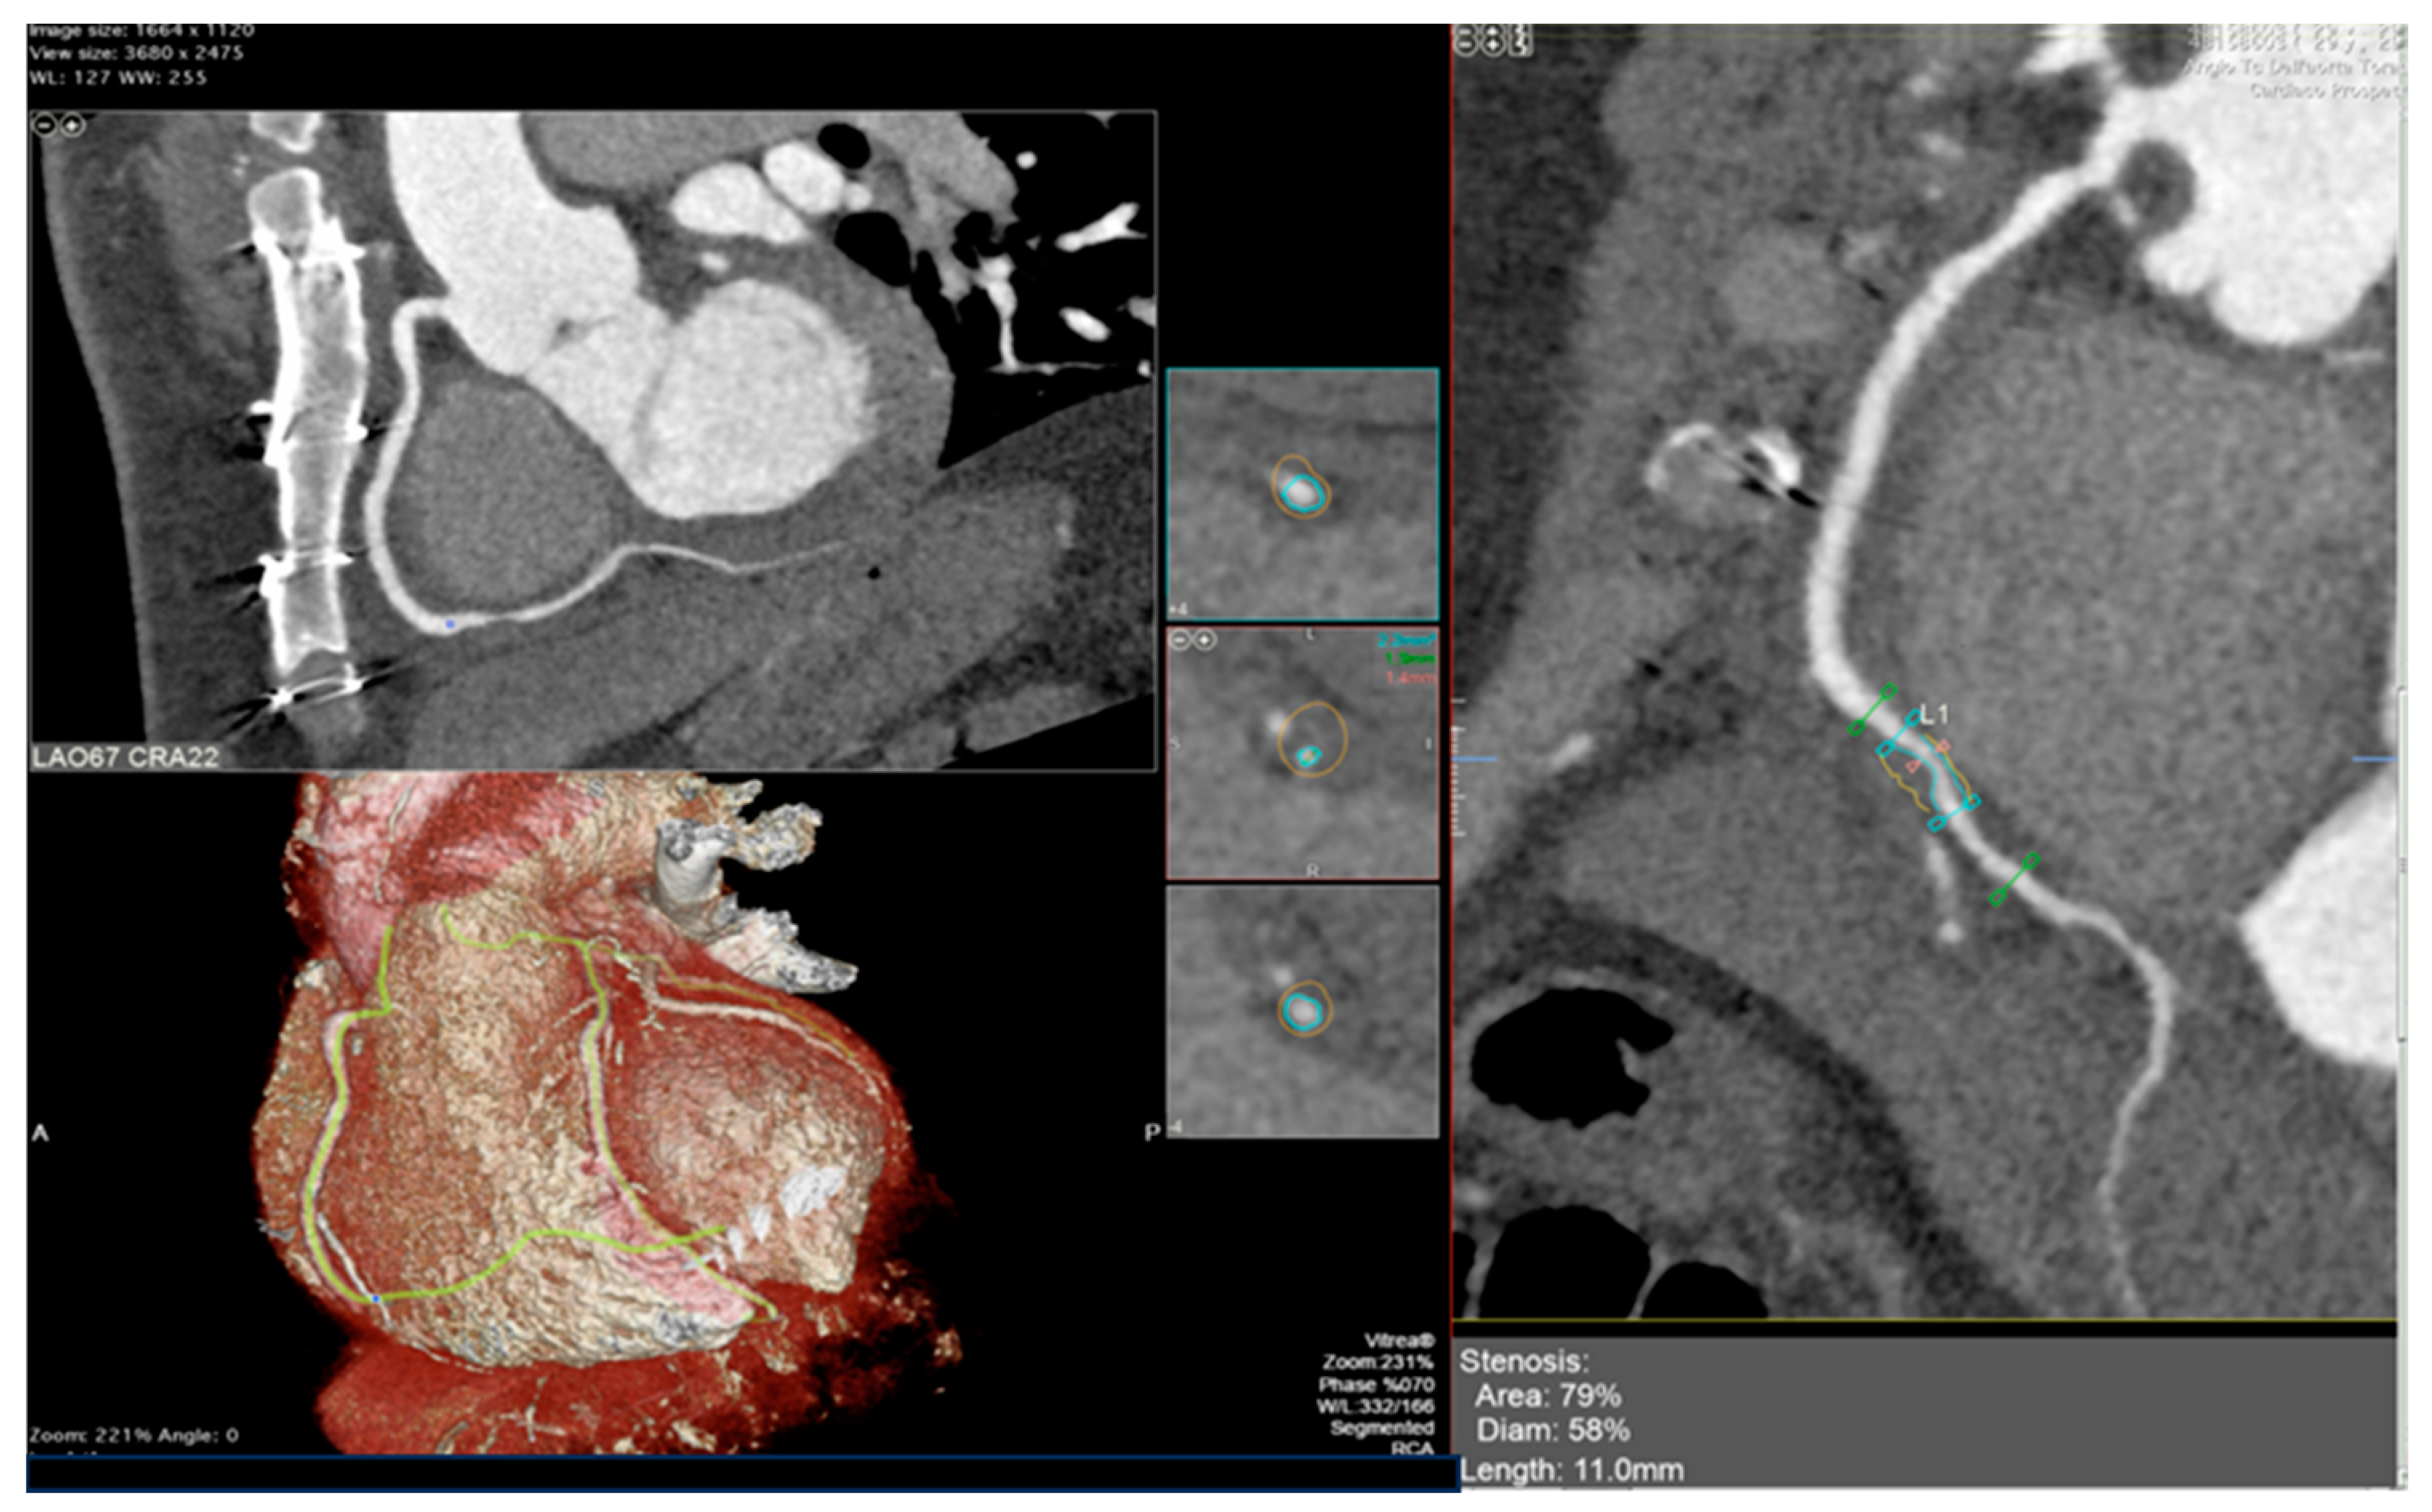

The integration of intravascular ultrasound (IVUS) with ICA reveals approximately 19% more cases of CAV, making it the most sensitive test available for monitoring CAV progression in the clinical setting [55]. However, CCTA has been proposed as an alternative to IVUS for routine follow-up of HT patients due to its superior spatial resolution [56]. In a recent meta-analysis, the sensitivity, specificity, positive predictive value, and negative predictive value of CCTA for detecting CAV were reported as 97%, 81%, 78%, and 97%, respectively [57]. Nevertheless, there is currently no standard method available for the assessment of CAV on CCTA images, and distinguishing CAV from atherosclerotic lesions can be challenging (examples in Figure 2 and Figure 3).

Figure 2. Cardiac computed tomography images showing cardiac allograft vasculopathy grade III according to the International Society for Heart and Lung Classification. Right coronary artery reconstruction with a calcific coronary plaque at the second tract assessed with cardiac computed tomography angiography (right panel) and his orthogonal views (left panel).